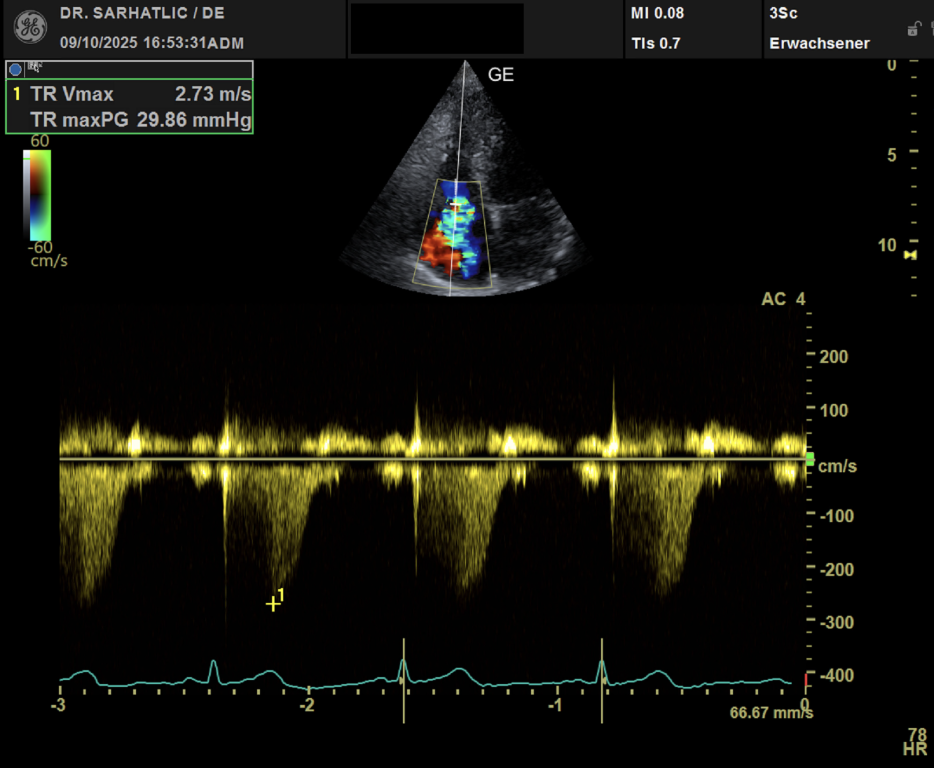

MODERNE ULTRASCHALLDIAGNOSTIK- Modernes Farbdoppler-Ultraschallgerät

- Hochauflösende Schallköpfe

- Ultraschall des Herzens (Echokardiografie)

VORSORGE-SCHWERPUNKTE- Herz- & Kreislauf-Vorsorge